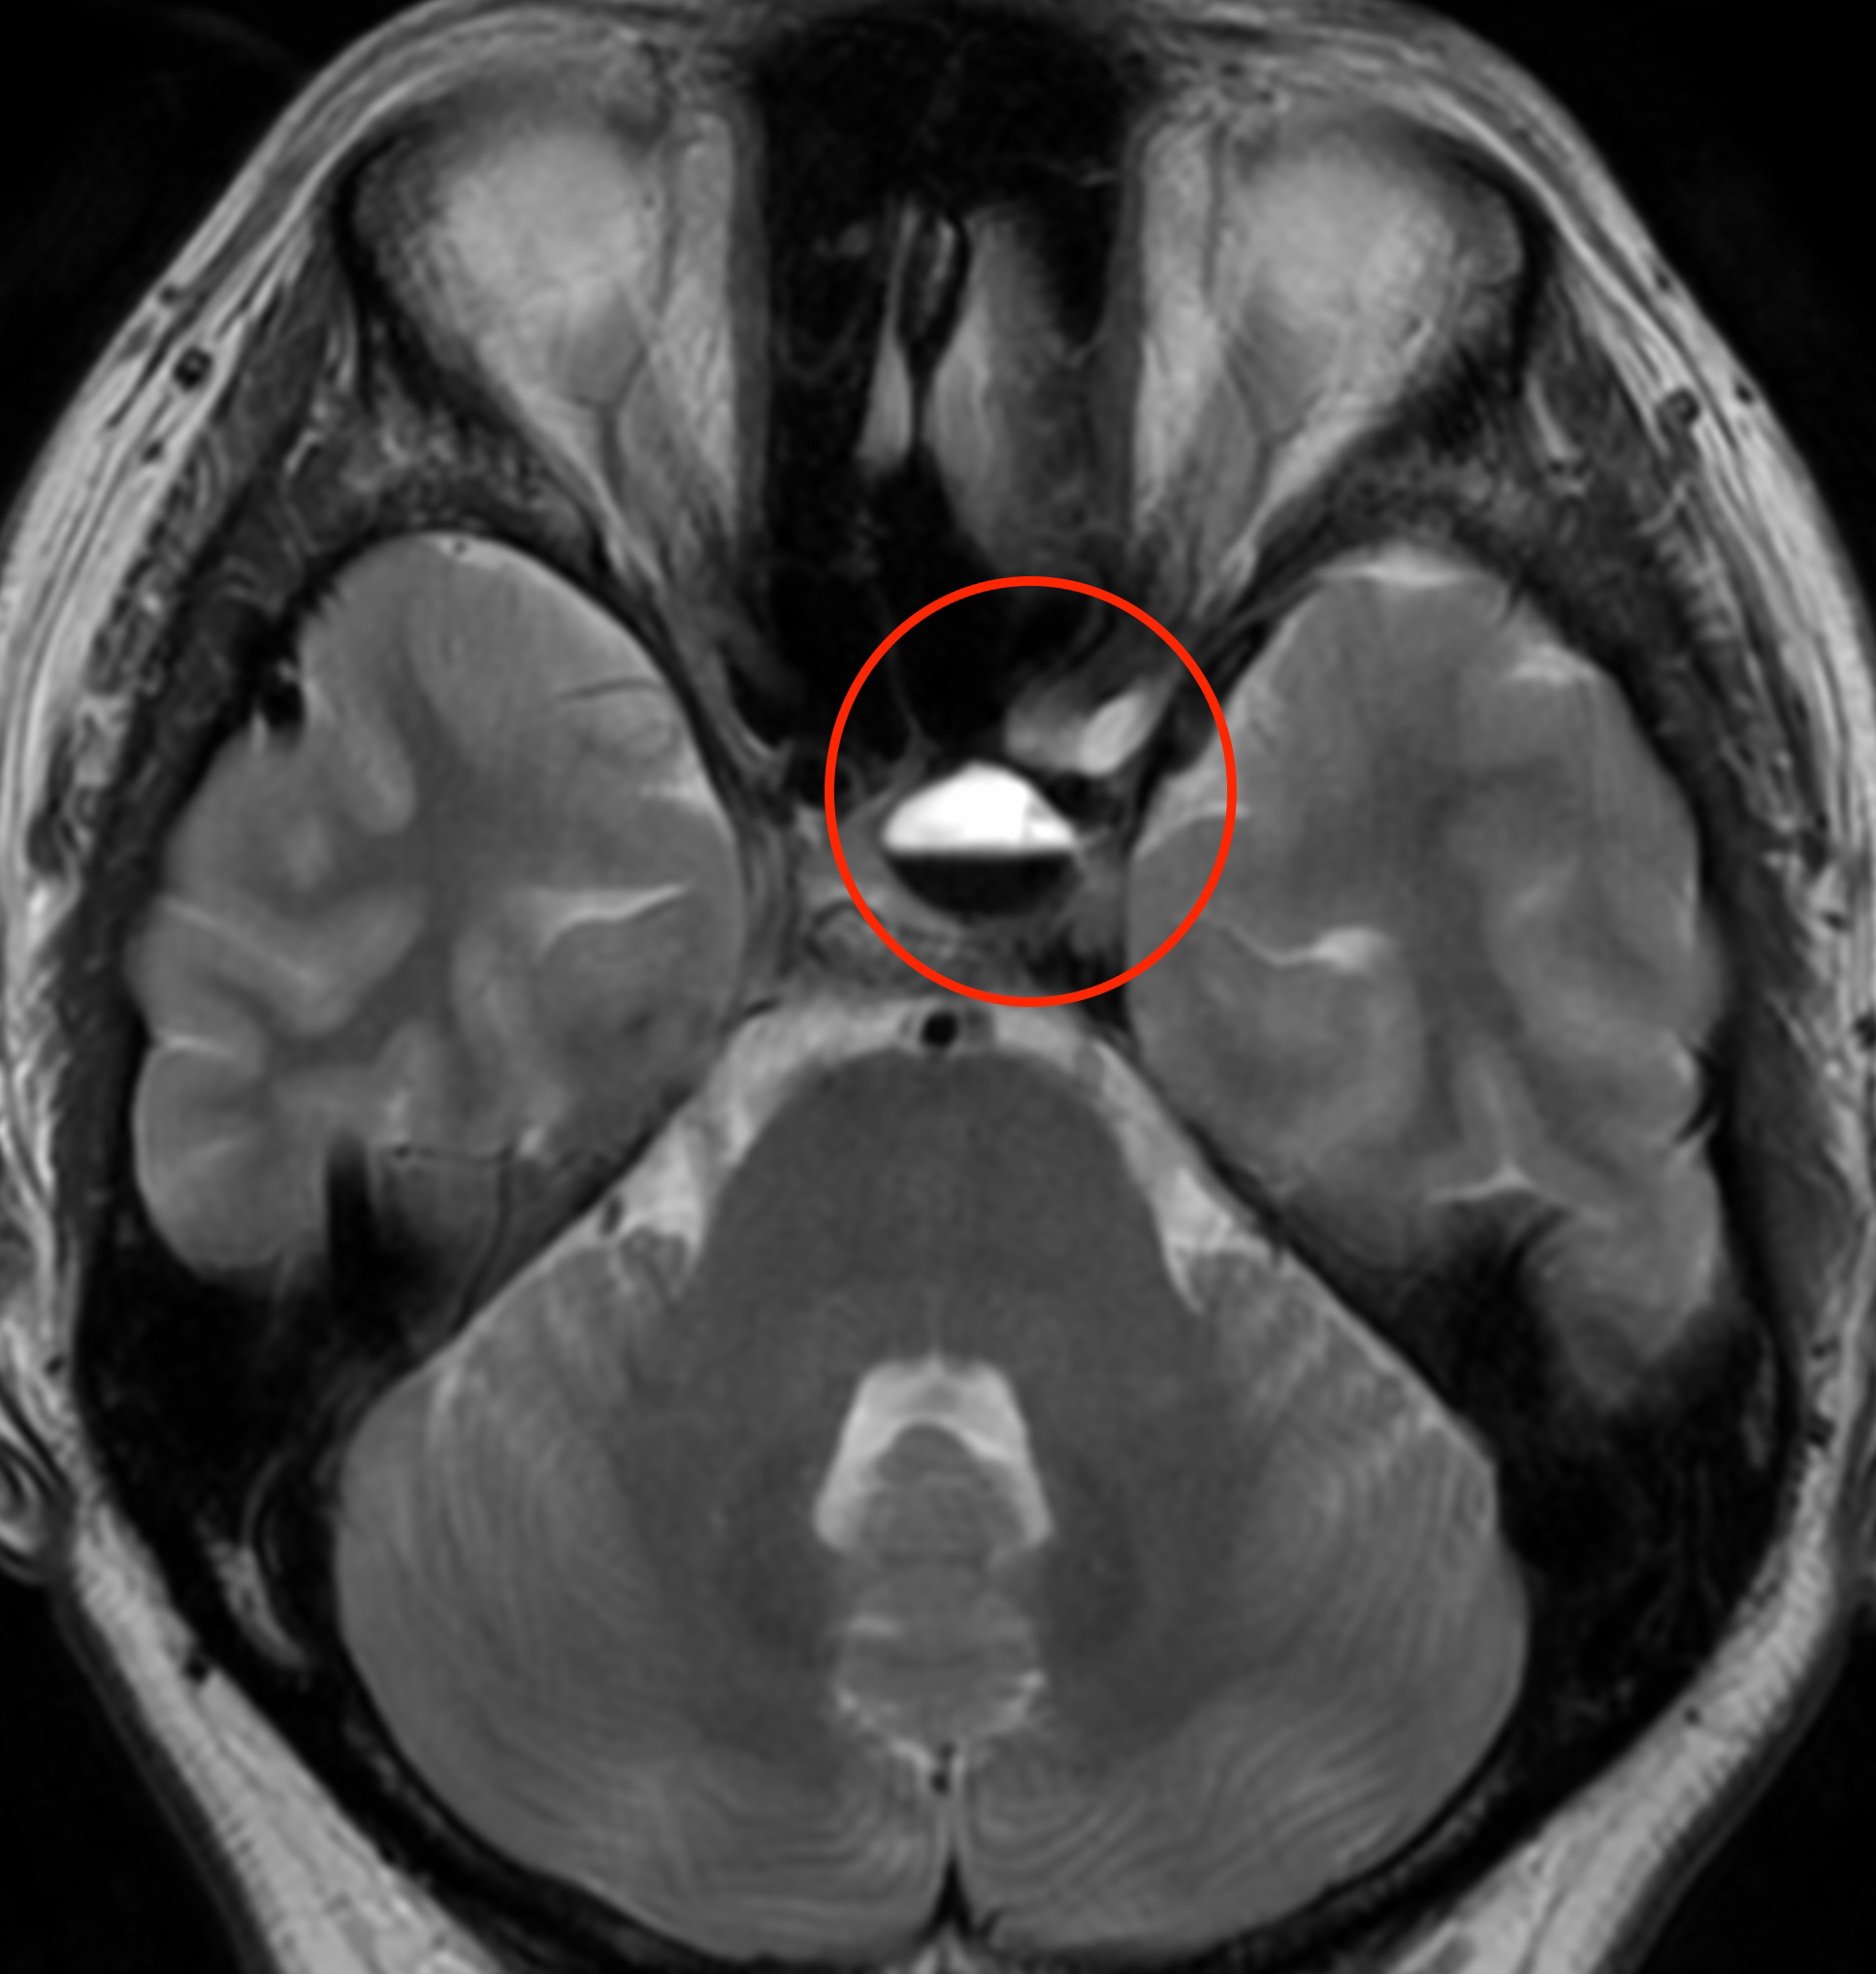

MRI検査で脳の血管を見たところ、

脳底動脈という血管の一部がくびれて細くなっており、その下の部分では、血管がソーセージのような形に膨らんでいます。そこで、この所見から可逆性脳血管攣縮症候群(RCVS)と診断しました。